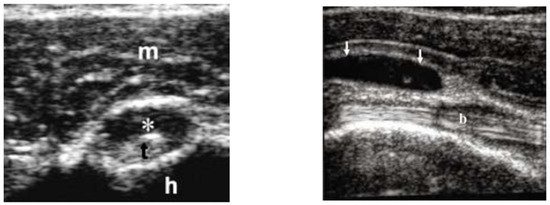

- US and 18-FDG PET/CT evaluations might increase diagnostic rates of ESR and CRP negative PMR.